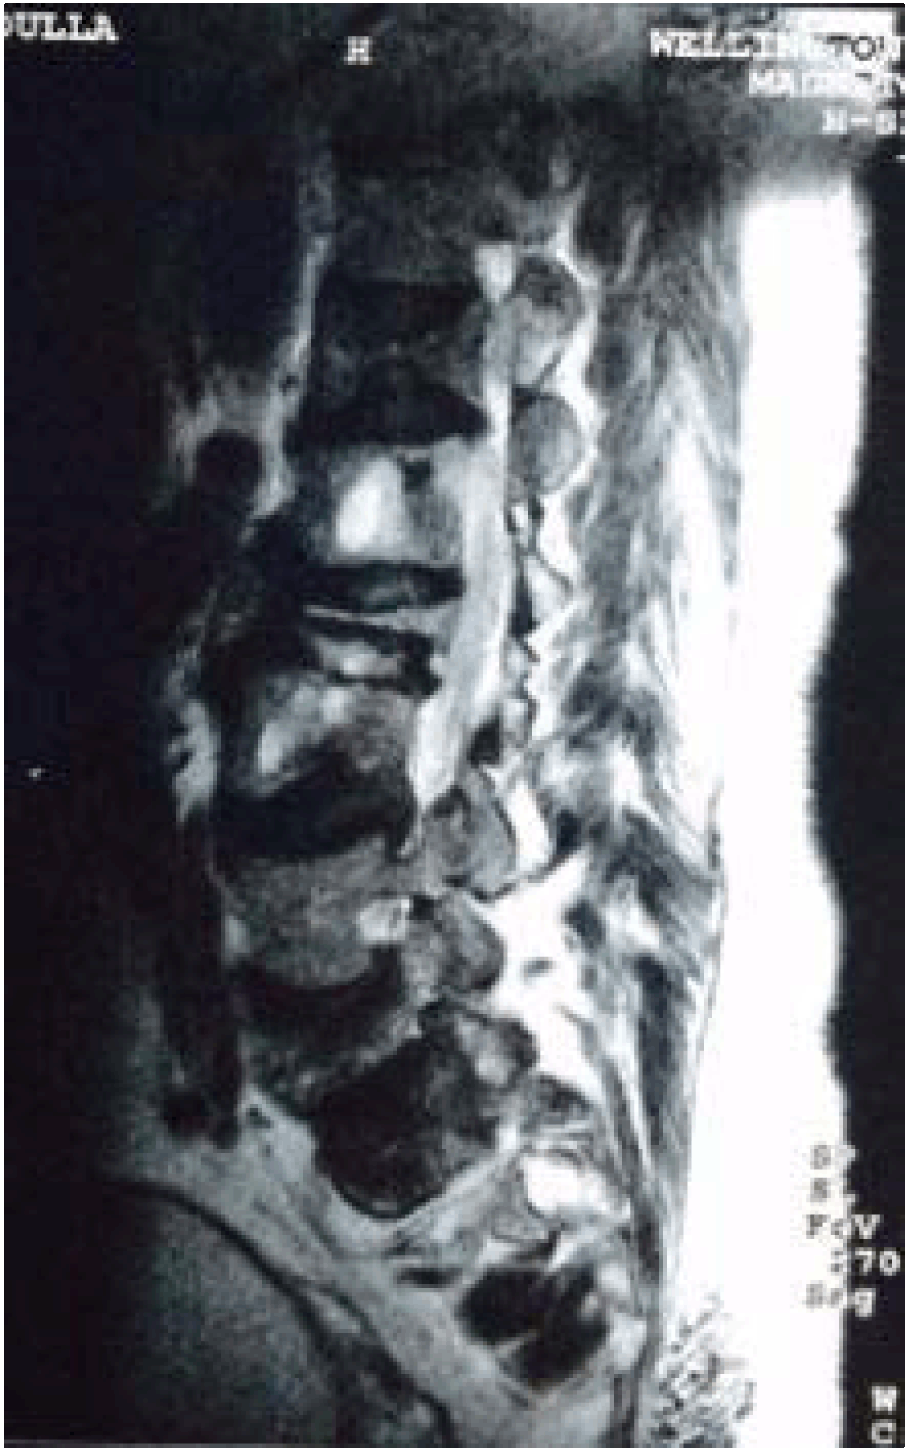

The patient had a repeat CT scan, MRI scan (Figure 5) and bone scan followed by one close and one open biopsy. However, although the slides were reviewed by multiple pathologists, no definitive conclusions could be made and the possibilities of Paget's disease and fibrous dysplasia were entertained with majority favoring Pagets's disease. No surgical intervention was undertaken and the patient was called for review after six months.

Figure 5: Magnetic resonance imaging T2-weighted image sagittal section of lumbar spine showing collapse of multiple vertebrae with altered signal intensity in both lumbar and sacral vertebral bodies. There is also narrowing of the spinal canal at multiple lower lumbar levels.